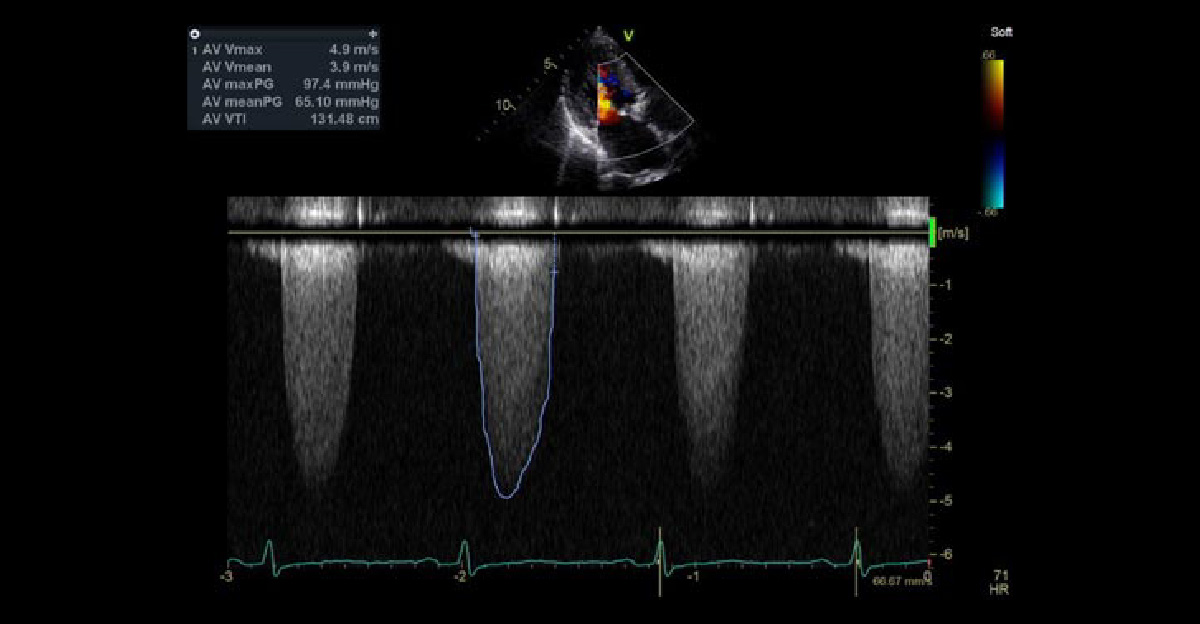

大動脈弁狭窄症

心臓弁膜症の中で、最も重要疾患となる、大動脈弁狭窄症です。意識消失や狭心症のような症状と関連して、突然死に至ることもあります。左室流出路最大血流が、4m/sを超えると、弁置換術の治療選択を考慮しながら管理します。

心エコー3腔像

心エコー5腔像